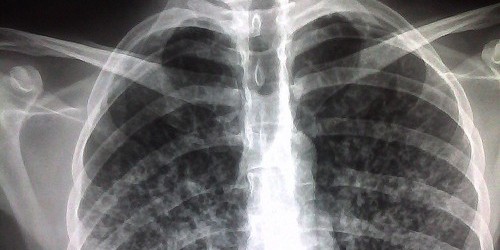

In most people, medication will cure tuberculosis if the correct drugs are taken for the right amount of time, and it can take up to 12 months to cure it successfully. All of the regular treatments have similar side effects, mostly related to digestion troubles and many people have no, or minor, side effects. Rifater, one of the most used medications in treatment of tuberculosis, can cause diarrhea, dizziness, drowsiness, or stomach gasses, but if you experience severe allergic reactions, se that your skin or eyes have turned yellowish or have fever for three or more days then it’s necessary to see a doctor immediately, stop he could eventually stop or change the treatment.